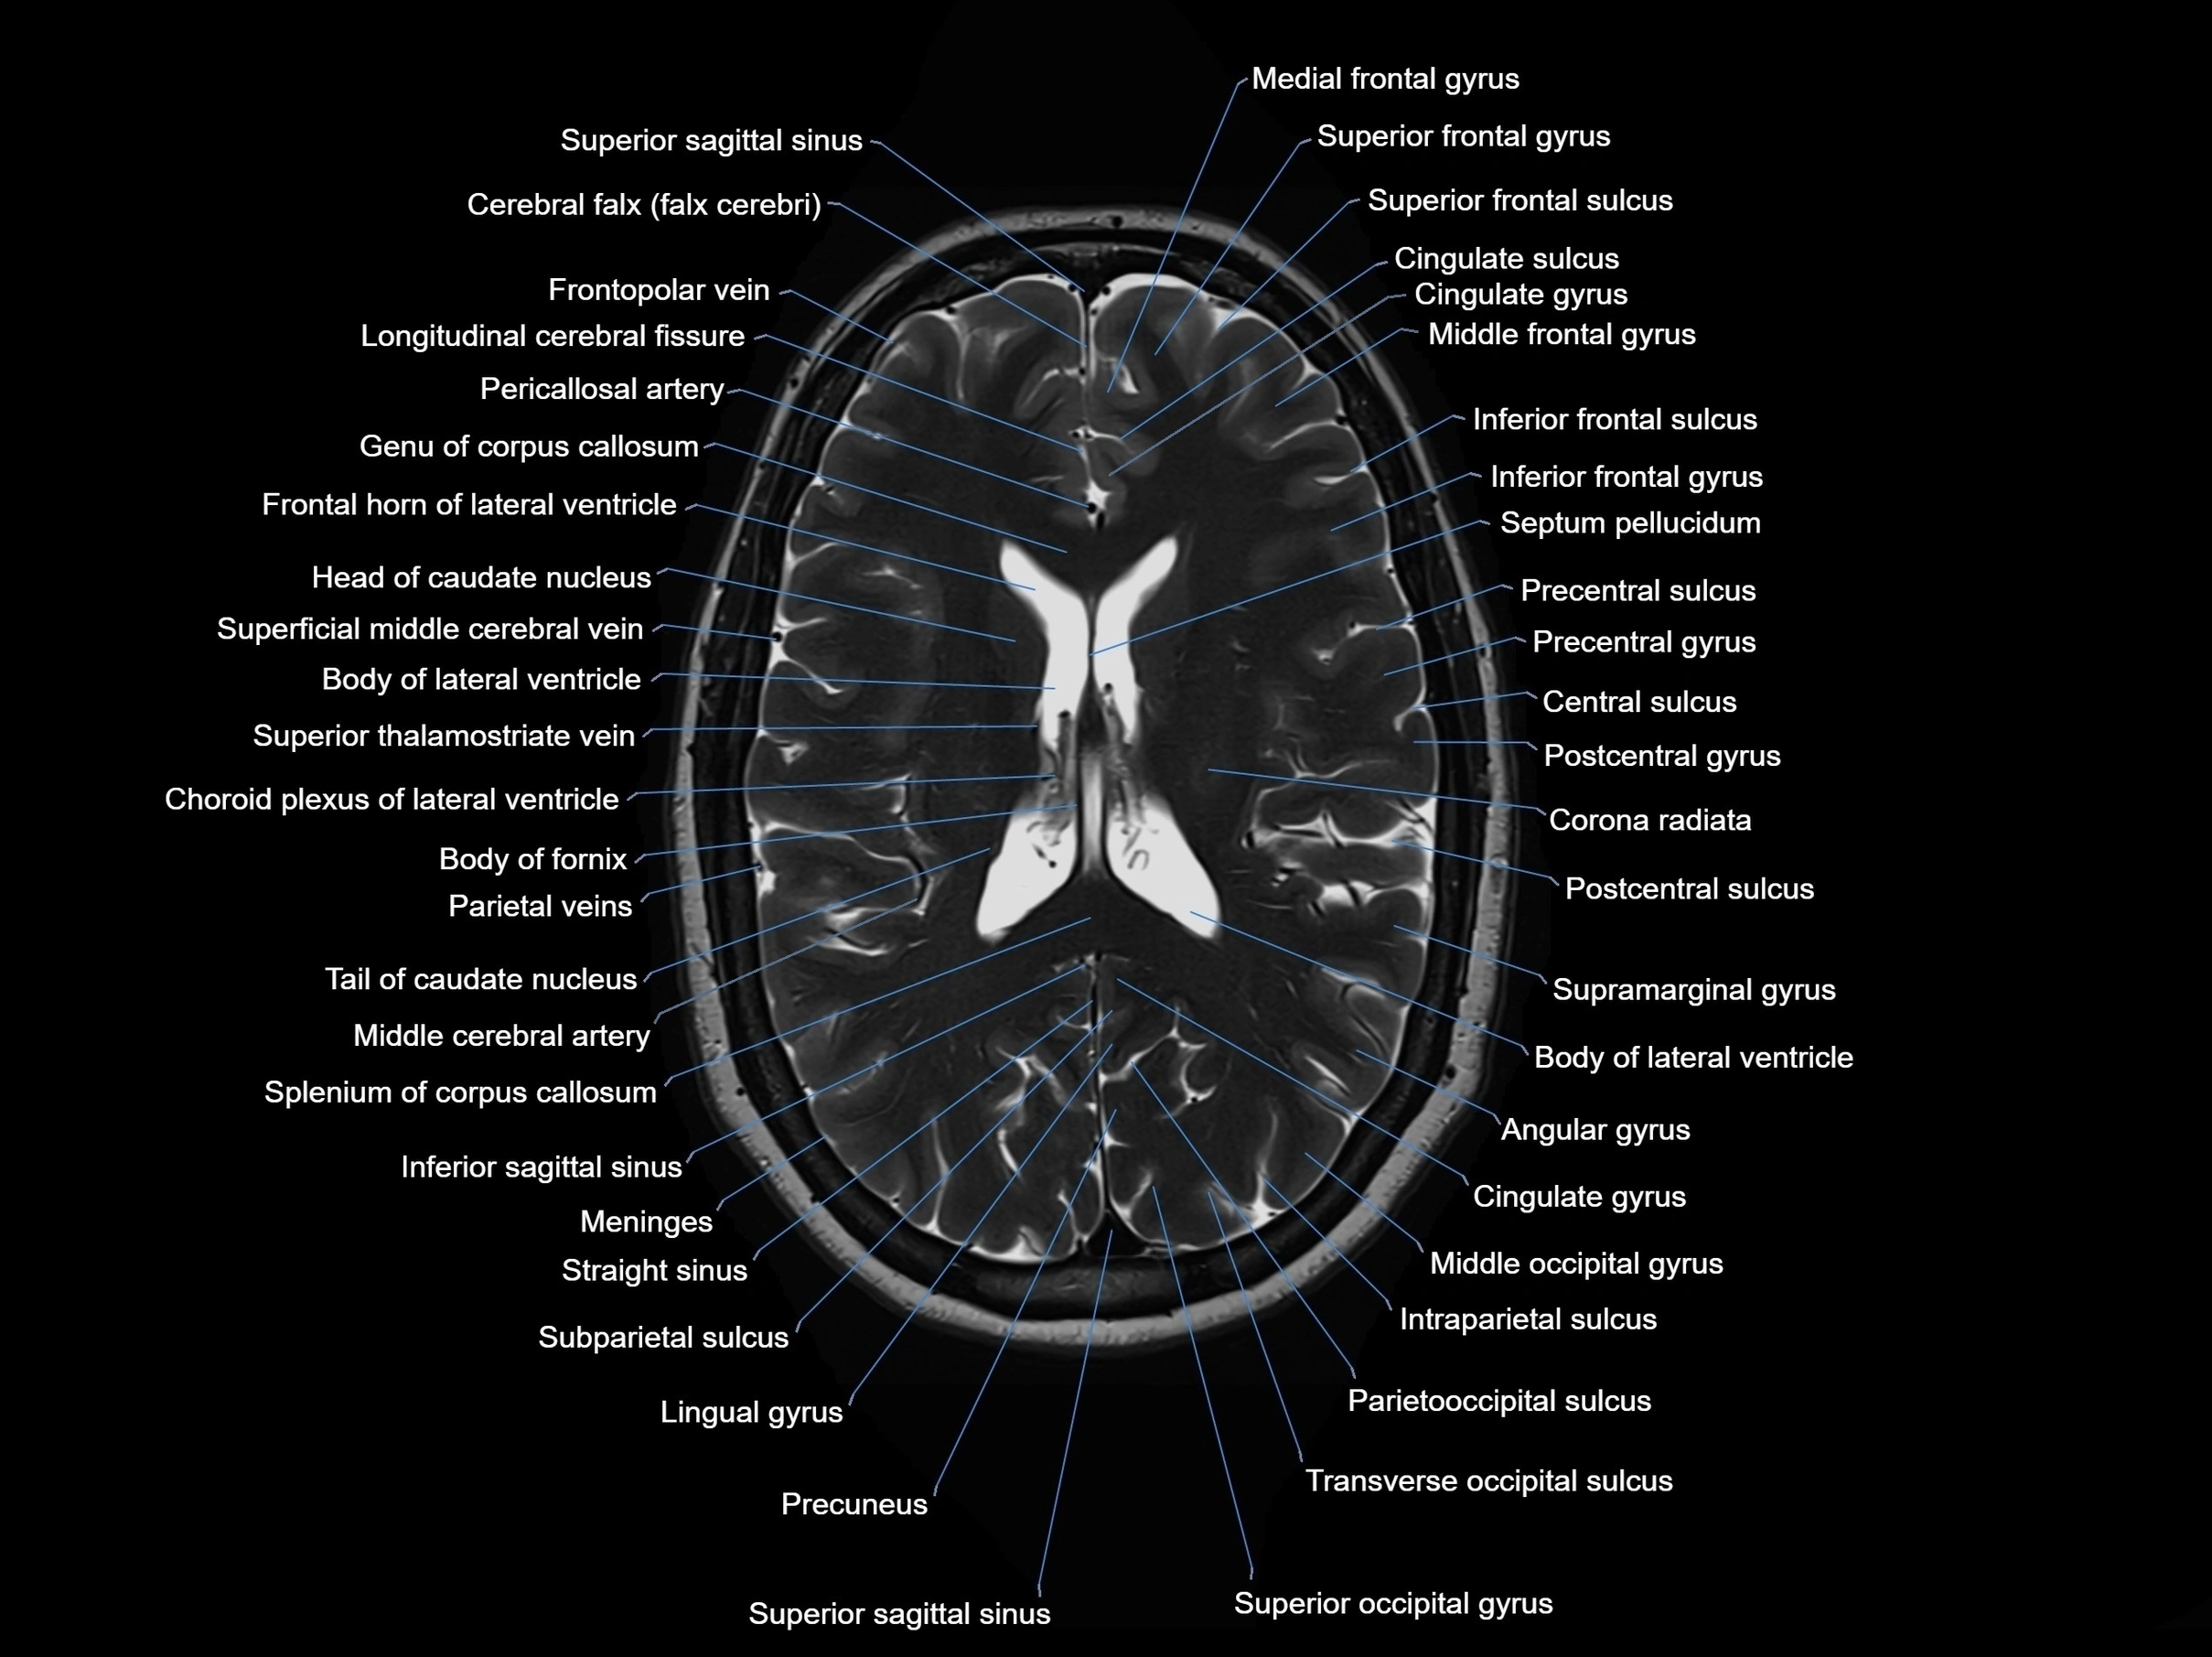

MRI images